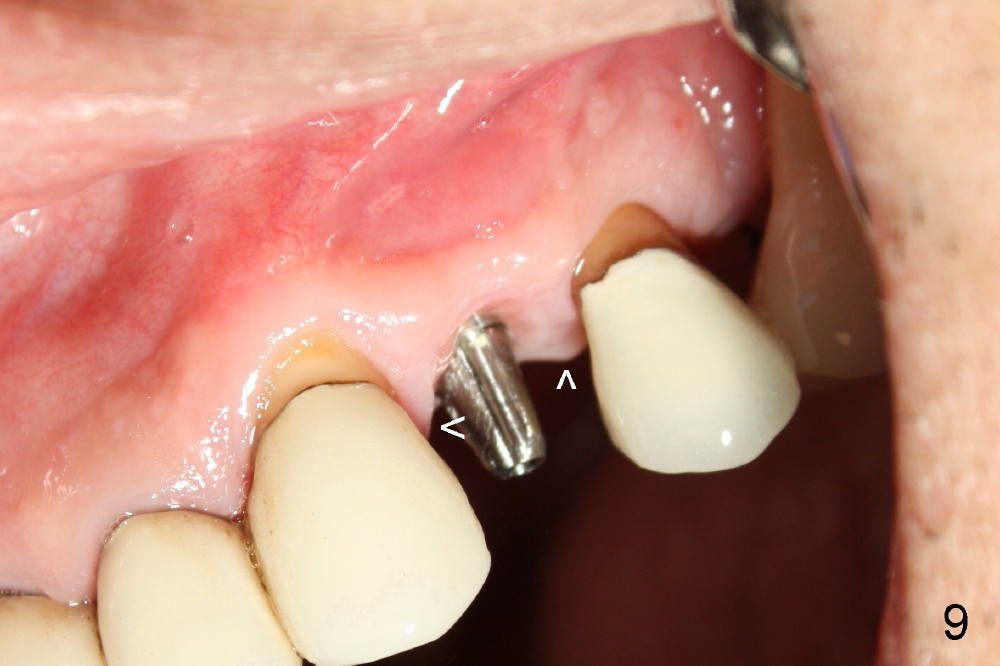

A 50-year-old man has mild pain in the upper left 1st bicuspid 3 years after root canal retreatment with placement of two posts (Fig.1). Findings of clinical exam are consistent with root fracture (Fig.2). Extraction reveals two fused roots (Fig.3,4). Probing indicates that the buccal plate is defective. Osteotomy is initiated in the palatal socket with a 2 mm pilot drill, followed by 2.5 and 3.0 mm reamers and 4.5x20 mm tap. The septum appears to have been pushed buccally (Fig.5 *) and form a new buccal wall (partially, strengthened by bone graft mentioned below) for the implant to be placed. The implant (4.5x20 mm) is placed in the palatal socket (Fig.6 *) with insertion of an abutment (A: 3.5x5 mm 0º), while a mixture of autogenous bone (harvested from reamers) and Synthograft (Bicon) is placed in the shrunken buccal socket (Fig.7; using allograft may decrease postop bony shrinkage). The bone graft is then contained by an immediate provisonal without collagen membrane or flaps. The patient is doing well postop. The gingiva is healthy (Fig.8*) when the provisional is removed 3 months postop with normal papillae (Fig.9 arrowheads). It remains the same 1 month post cementation (Fig.10,11). For further follow up, see immediate implant of the tooth #13.